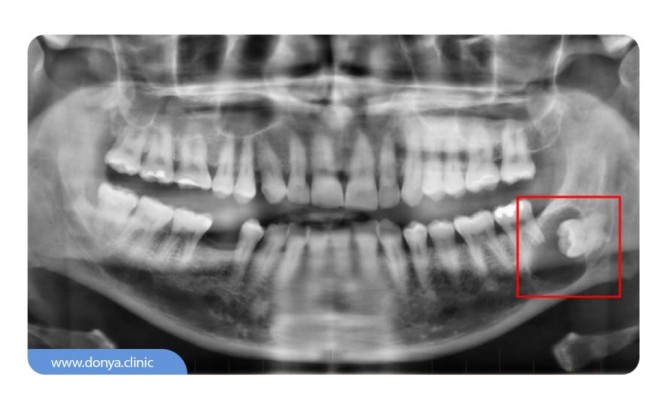

عکس دندان در شاهین شهر

علم رادیولوژی شاخه ای از علم پزشکی است که برای تشخیص و همینطور درمان بیماری های جسمی استفاده می شود.